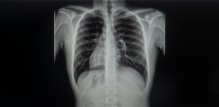

dekstrokardija Budite prvi i komentirajte! 1 min čitanja Maja Kuzelj Grgić mag. comm., univ. bacc. croat. Tekst Dana Za vas izdvajamo Evo što kaže onkologinja Kada starije žene mogu prestati s mamografskim pregledima? Tomislav Stanić 2 min čitanja Članak objavljen: 04-02-2026 Zatvori Podijelite članak Facebook Twitter Whatsapp Viber Kopirajte adresu